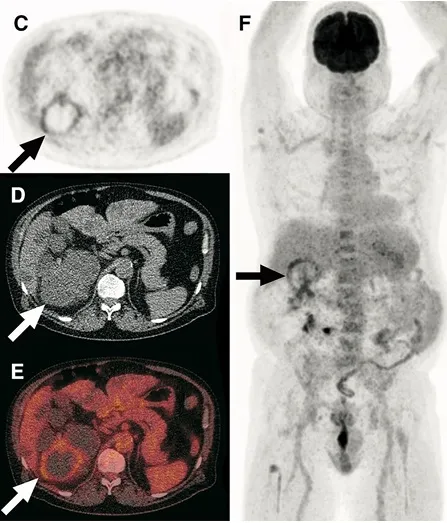

Hiperlipidemia na Nefropatia Membranosa: Um novo olhar que impacta no tratamento

A dislipidemia na Nefropatia Membranosa sempre foi tratada como dano colateral da síndrome nefrótica. Essa revisão muda a pergunta — e muda o que fazemos com ela.